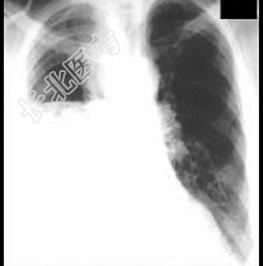

- 单项选择题女性,36岁, 2个月前突然发热、咽痛、咳嗽、少量黄痰,经消炎治疗不见好转, 一个月前,咳嗽加剧, 并有呼吸困难,经两次胸穿抽出脓液300ml, 症状不见好转,胸片如图, 提示右侧胸腔有一液平,现应采取的治疗方法 ( )

D、腋中线第7肋间闭式引流